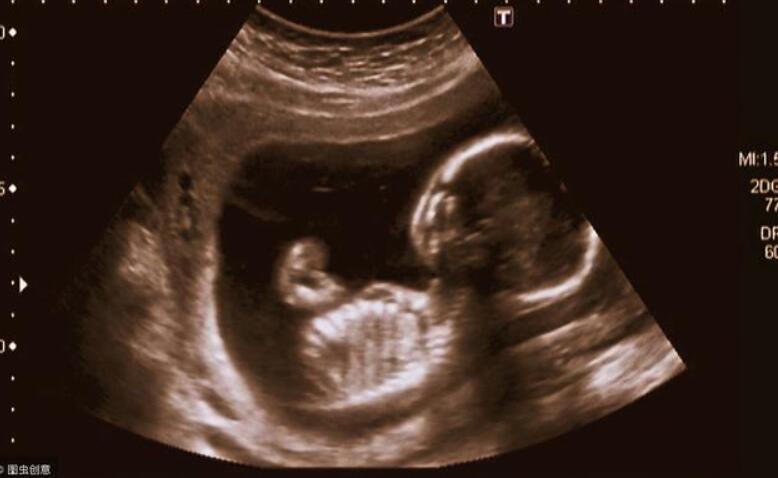

首先,在怀孕大概28周左右的时间里,胎动会越来越频繁,时间也相对固定,一般12个小时左右的时间里会达到30次左右,而且,随着子宫里的活动空间越来越小,胎儿的活动空间也会越来越小,只能慢慢挪动,

到了孕晚期,最容易发生的情况就是胎儿脐带绕颈导致的缺氧,一般,在胎儿36周以后,每周都要做胎心监护,还要密切的注意胎儿的动向,生怕一个不小心就会造成胎儿缺氧,